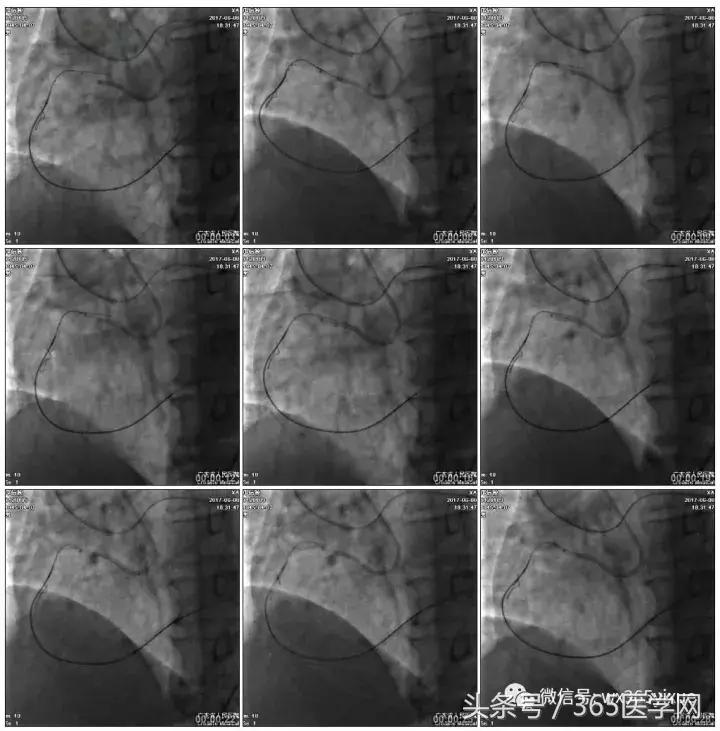

2.Guidezilla延长导管辅助下,逆向导丝进入正向GC

1.更换RG3导丝

2.GC送入普通导丝,保护LM

RCA闭塞段球囊扩张后IVUS

支架术后造影结果

支架术后IVUS